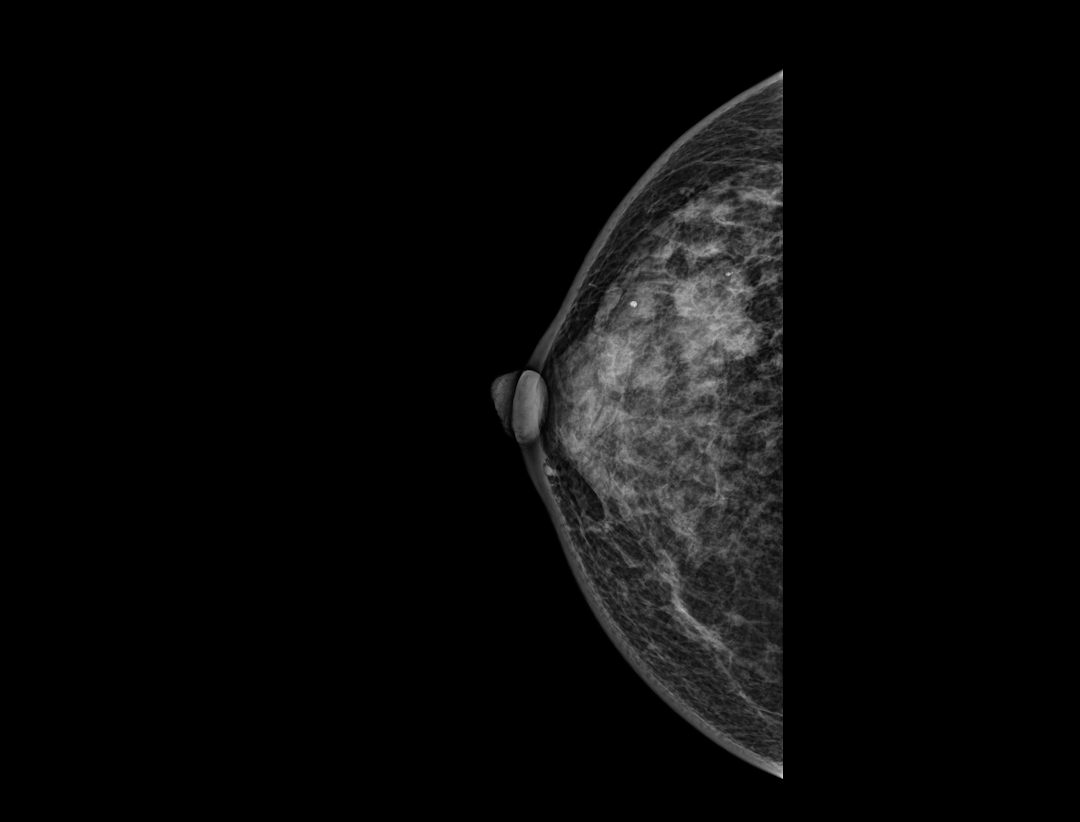

对比增强引导

穿刺活检

“一步到位”精准取样,助力高效诊断